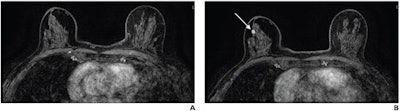

(A) Axial subtracted contrast-enhanced fat-suppressed T1-weighted image from a baseline abbreviated MRI examination is negative (BI-RADS category 1). (B) Axial subtracted contrast-enhanced fat-suppressed T1-weighted image from a subsequent-round abbreviated MRI examination performed two years later shows a new 5-mm enhancing mass in the upper outer right breast (arrow), which was not seen on a mammogram performed five months prior. The exam was assessed as BI-RADS category 5. Ultrasound-guided core biopsy yielded invasive ductal carcinoma (ER+/PR+/HER2-). Image courtesy of the ARRS.

Edmonds and colleagues found that all 45 cancers diagnosed by baseline or subsequent-round abbreviated MRI were stage 0 or 1. Seven cancers diagnosed by subsequent-round abbreviated MRI had the following characteristics: an average interval since prior examination of 872 days, size of 0.3 to 1.2 cm, and node-negative status at surgical axillary evaluation.